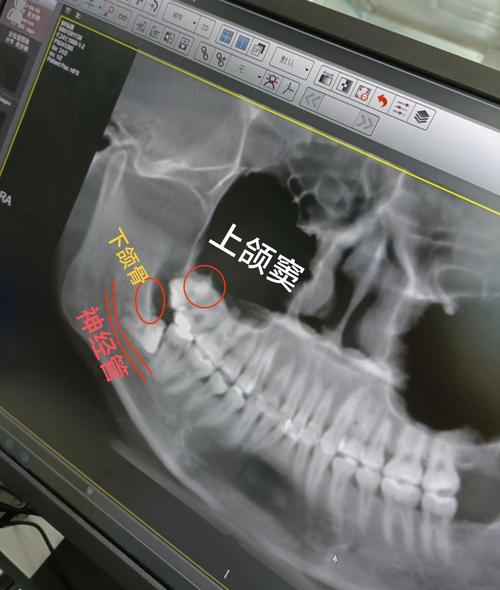

正畸前的风险评估与预防是关键环节,在正畸设计初期,应通过全口曲面断层片、CBCT等影像学检查评估智齿位置、萌出方向及与邻牙关系,对于存在高危因素的患者(如智牙胚近中角度>30°、与第二磨牙间距<5mm、牙弓后段拥挤),可考虑在正畸治疗前预防性拔除智齿,尤其当正畸方案需拔除前磨牙时,提前拔除智齿可避免其与后牙段移动的相互干扰。